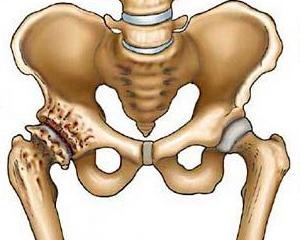

Механизм развития коксартроза

Тазобедренный сустав представлен двумя костями: головкой бедренной кости, которая катается по вертлужной впадине (последняя похожа на неглубокую пиалу или лузу).

Сверху они покрыты специальным суставным хрящом. Он напоминает губчатое вещество: расправляется при отсутствии движения в суставе и сжимается при движениях. При его сжимании в сустав выжимается специальная жидкость, которая и является смазкой для сочленяющихся костей. Кроме того, сам хрящ прекрасно амортизирует движения, равномерно распределяет нагрузку на весь сустав.

При коксартрозе нарушается питание самого хряща. Он истончается, а затем исчезает островками. Если процесс не остановить, в местах атрофии хряща разрастается кость, которая пытается «заполнить» пустоту. В результате развиваются костные «шипы» – остеофиты. Это приводит к нарушению конгруэнтности сочленяющихся костей, «стиранию» оставшихся участков здорового хряща.